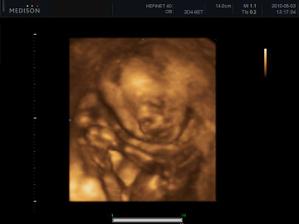

Náš zázrak